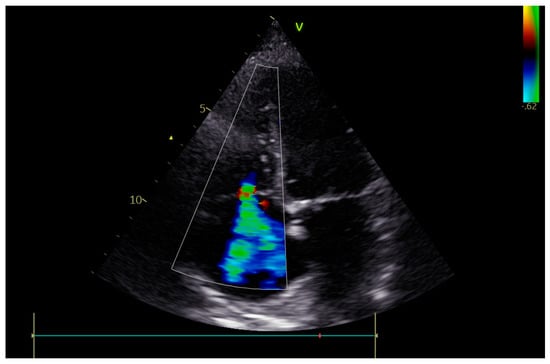

2. Case Report

3.3. Valvular Defects